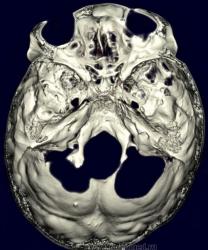

Метастазы в костях основания черепа.

Женщина средних лет с клиникой невралгии тройничного нерва справа. На КТ были выявлены округлые очаги деструкции в костях основания черепа (средней черепной ямки).

Наблюдение Nela.